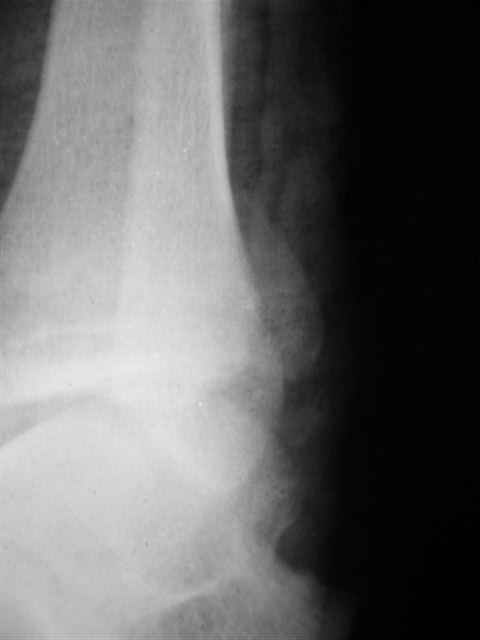

Уважаемый Иван,

Я предупреждал, что ничего сверхъестественного. Каюсь, что одна из спиц прошла несколько дальше, чем нужно было, но главное - перелом стабилизирован и больной работает суставом в полном объёме, несмотря на представленную раннее травму коленного сустава.

Всего вам Доброго,

Евгений И Чекашкин